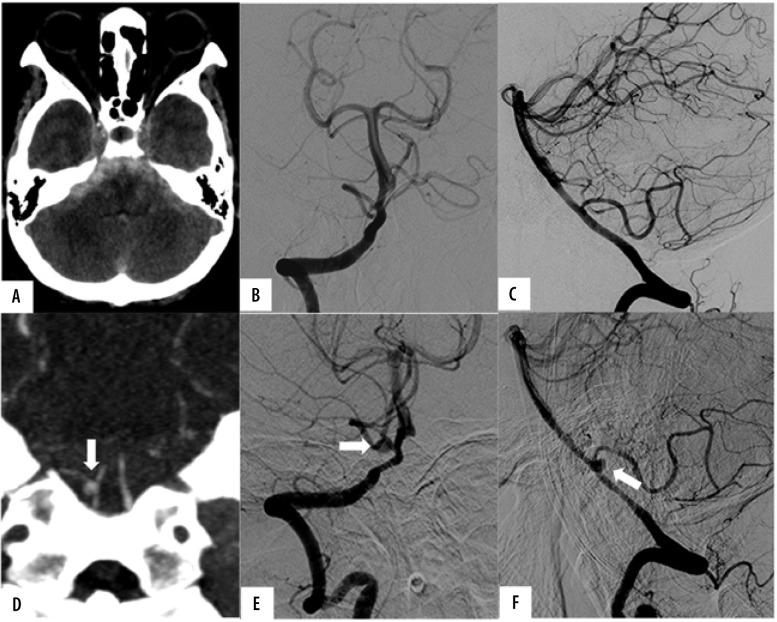

Results: Forty-seven patients were included in our study, with a median age of 55 years and a range of 28-81 years. Thirty-seven had diffuse SAH (66%), and 16 had perimesencephalic SAH (34%). The repeat CTA revealed 2 causa-tive vascular lesions (a right PICA aneurysm and a mycotic aneurysm) in 2 separate patients (yield of 4.3%), both of whom had diffuse SAH (yield of 6.5%). In retrospect, none of these vascular lesions were evident in the initial CTA and DSA. No evidence of re-bleeding was observed in the follow-up period.